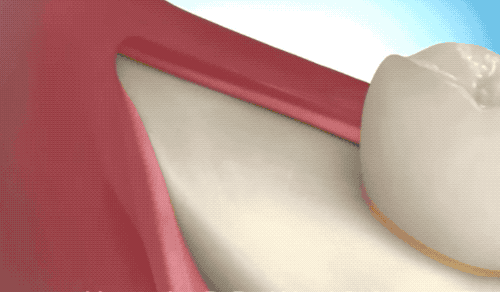

難度二地獄模式

這種款式的橫阻生智齒。一般生長(zhǎng)情況也分兩種,一種是已經(jīng)出肉的,一種是還未出肉的,操作都差不多,我們就直接看下圖的介紹了。

露出牙槽骨后,先削除一部分骨頭,露出躺臥如睡美人的橫阻生智齒...如果是已經(jīng)出肉的智齒,就沒(méi)這一步了。

請(qǐng)出那令人聞聲喪膽的牙科渦輪機(jī),先分割智齒,撬出塊頭過(guò)大的牙冠來(lái)...再把牙根磨切兩半,依次撬出來(lái)。